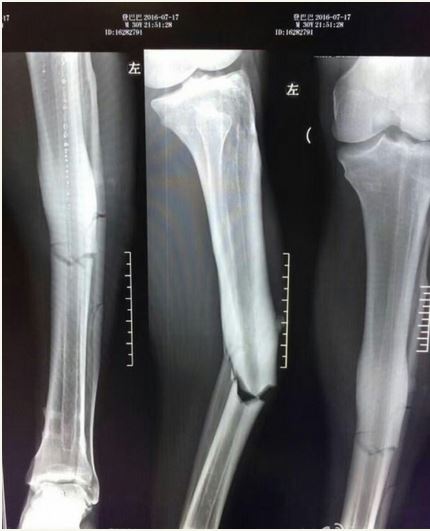

X-ray of Ba’s broken leg